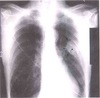

What is this CXR showing?

* Right pleural effusion * Notice the loss of the costophrenic angle